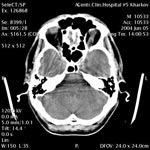

Ишемический инсульт Ишемический инсульт

Пациент С., 44 года

Объемный процесс параселлярной области слева.

ЦКБ5 Южной железной дороги, отделение лучевой диагностики.

Протокол.

На КТ-сканах вещество головного мозга без очаговых изменений, плотностью 24-37 HU. Срединные структуры головного мозга не смещены. Слева параселлярно слабо гиперденсивный очаг размерами 13х11 мм, асимметрия прилежащих отделов спинки турецкого седла (краевой дефект). Желудочки мозга обычной формы, слегка расширены (ширина III желудочка - 5мм, передних рогов боковых: правого 8 мм, левого 10 мм). Конвекситальные подпаутинные пространства сглажены. Сильвиева щель слева слабо дифференцируется. Цистерны мозга не расширены. Субтенториальные структуры без особенностей. Селлярная область не изменена. Пневматизация основной, фронтальной пазух и клеток решетчатого лабиринта не нарушена. Заключение: нельзя исключить объемный процесс параселлярной области слева (необходимо дифференцировать аневризму ВСА и внемозговую опухоль). С учетом клиники, анамнеза, нельзя исключить субарахноидальное кровоизлияние. Показана КТ с контрастным усилением. На КТ-сканах в условиях контрастного усиления (ультравист 300-100,0 в/в болюсно) определяется мешотчатая аневризма супраклиноидного отдела левой ВСА, исходящая из латеральной стенки на 7 мм проксимальнее бифуркации размерами 6х3 мм, с наличием шейки диаметром 2 мм. Дно аневризмы расположено латерально и незначительно кверху по отношению к шейке.